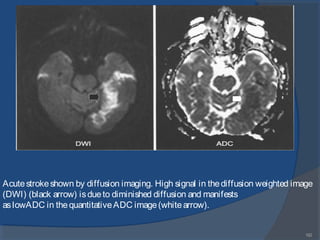

Diffusion images. When diffusion-sensitizing gradientsareadded to

theTI-weighted EPI image(left), adiffusion-sensitized or diffusion-weighted image

(DWI) (center) results. Themagnitudeof diffusion can bequantified and displayed

asan ADC image, often called an ADC map (right).

Acutestrokeshown by diffusion imaging. High signal in thediffusion weighted image

(DWI) (black arrow) isdueto diminished diffusion and manifests

aslowADC in thequantitativeADC image(whitearrow).